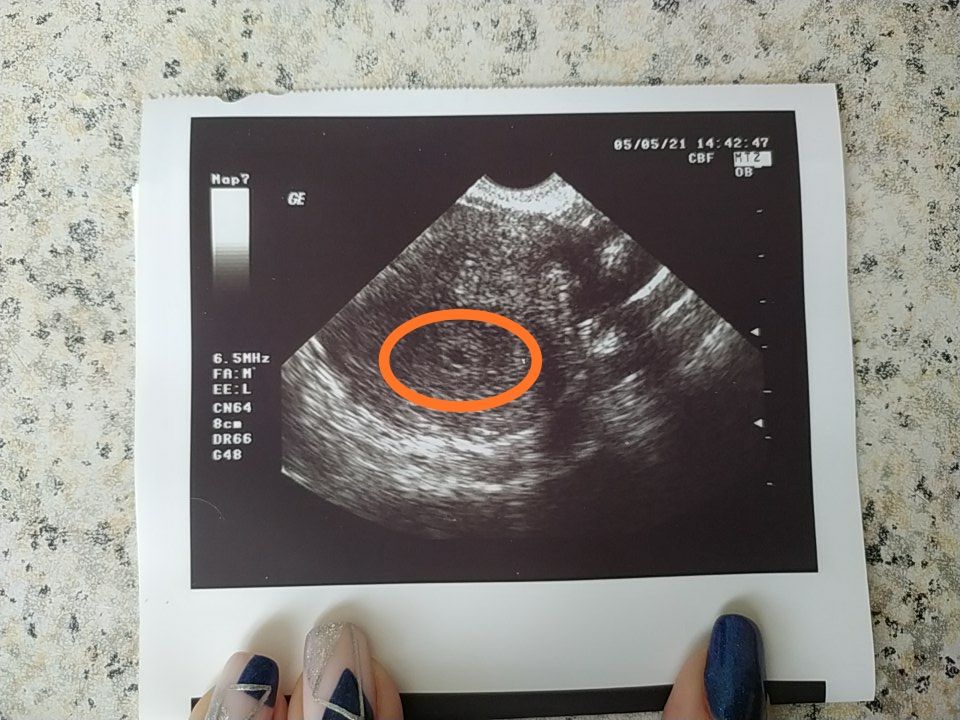

Сегодня ходила снова на узи, врач увидел чёрную точку, сказал, похоже на беременность! Как думаете, беременность? Срок акушерский 5 недель... Тест электронный показал 2-3 недели)

По тесту тоже у вас 5 недель) это очень хорошо видно же))) Тихонько поздравляю, берегите себя

Конечно, беременность :) тем более и тест показал) это плодное яйцо, эмьриончик покажется попозже 🧡

увидела прошлый пост, эндометрий тоже пышненький, беременный) почти 15 мм 👍